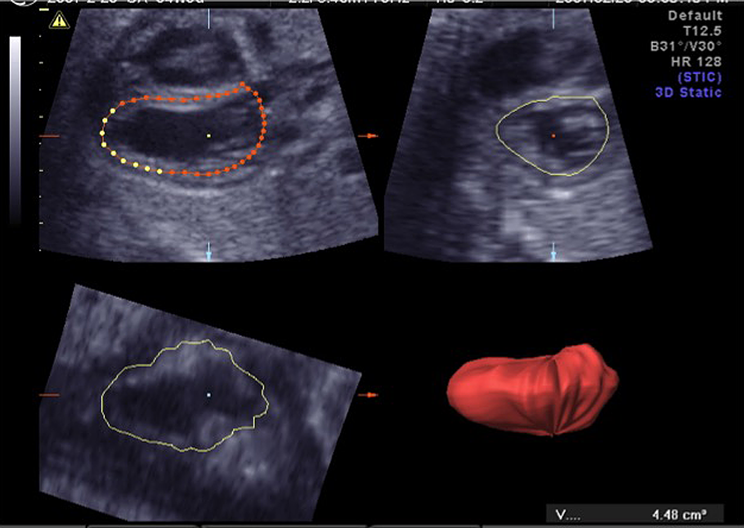

いわゆるレントゲンの心胸郭比に相当する,グローバルな心機能の指標である.計測には総心横径(total cardiac dimension: TCD)と心胸郭面積比(cardiothoracic area ratio: CTAR)がある.TCDは四腔断面において,三尖弁付着部の心外膜から僧房弁付着部の心外膜までを測定したもので,22週以降では数週mmが正常値とされている.CTARは四腔断面で心膜外側をトレースした心臓の面積を脊柱や肋骨を含み,皮膚や筋肉を含まない胸郭の面積で除して求められる (Fig. 1).簡便のため両方を楕円で近似したellipse法が多く用いられる.正常は0.20~0.35.

Fig. 1 Measurement of the cardiothoracic area ratio

A four-chamber view of the fetal heart. The thoracic area is indicated by a solid line, and the cardiac area was by a dotted line. (A: anterior, L: left, R: right, P: posterior)